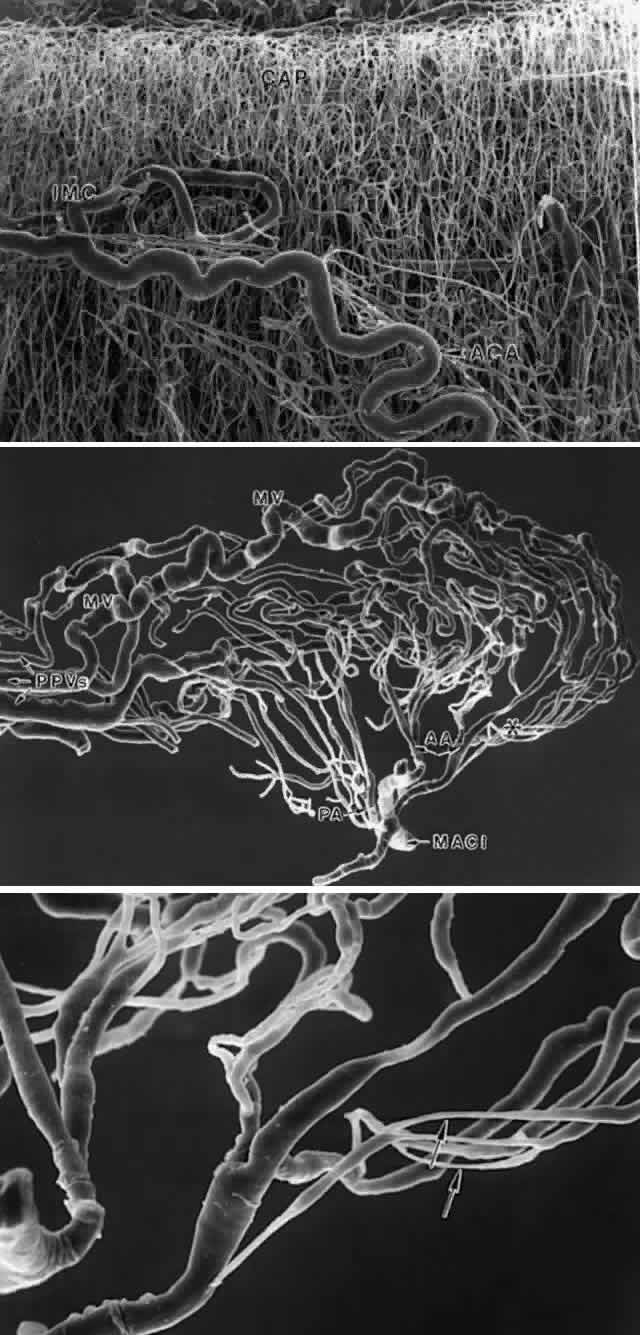

Studies on the ciliary body circulation, using scanning electron microscopy of methacrylate vascular casts, have greatly clarified this complex subject in recent years. The primate vasculature66–68 has been more extensively investigated than the human69,70but is sufficiently closely related to form a basis for understanding the human variations (Fig. 44). The blood supply to the ciliary body derives from two long posterior ciliary arteries and seven anterior ciliary arteries, two from each rectus muscle except for the lateral rectus, which provides only one. After leaving the rectus muscles, the anterior ciliary arteries send branches to form an anterior episcleral plexus around the corneal limbus.66,69 The remaining vessels divide into 10 to 20 branches before or after penetrating the sclera to enter the ciliary muscle, at the posterior border of the pars plicata. The lateral rectus vessel contributes only 0 to 2 branches. Within the ciliary muscle, an incomplete intramuscular circle or plexus is formed, primarily from branches of the anterior ciliary arteries with variable anastomoses to branches of the long posterior ciliary arteries.66–69 The intramuscular circle supplies particularly the outer and posterior part of the capacious capillary circulation of the ciliary muscle (see Figs. 44A, Figs. 45A) and sends recurrent branches back to join the peripheral choriocapillaris. Branches of the anterior ciliary arteries also supply the iris directly or from branches of the intramuscular circle and contribute to the major arterial circle of the iris.

Fig. 44. Diagram of ciliary body vasculature. A. Branches of anterior ciliary perforating artery (ACA) and long posterior ciliary artery (LPCA). ACA branches: 1. Branches forming the intramuscular circle. 2. Branch to MACI, especially contributing to the superior and inferior circle. 3. Branch to outer and posterior ciliary muscle. 4. Recurrent artery to peripheral choroid. 5. Branch to iris. LPCA branches: 6. Primary branches supplying the MACI. 7. Branch to the intramuscular circle. B. Major arterial circle of the iris (MACI) and its branches to ciliary process. 1. Arteriole to base and anterior edge of the ciliary process. 2. Arteriole directly to marginal venous sytem. 3. Arteriole supplying middle of ciliary process through venous capillaries to marginal venule. 4. Arteriole to posterior ciliary process and minor processes. 5. Marginal venule. 6. Arteriole to iris. 7. Iris vein. 8. Arteriole to anterior and inner ciliary muscle. 9. Pars plana veins. (Compiled from multiple sources: Funk R, Rohen JW: Exp Eye Res 47:653, 1988 and 51:651, 1990; Morrison JC, Van Buskirk EM: Ophthalmology 90:707, 1983; Am J Ophthalmol 97:372,1984; and Morrison, unpublished).

Fig. 45. Scanning electron micrographs of human ciliary body vasculature after injection with methylmethacrylate. A. Anterior ciliary perforating artery (ACA) to intramuscular plexus (IMC), supplying the profuse capillary bed (CAP) of the anterior ciliary muscle. (X 54) B. Vasculature of a single ciliary process, supplied by anterior (AA) and posterior (PA) arterioles from the major arterial circle of the iris (MACI). The dilated marginal venules (MV) are clearly visible along the crest of the process and, along with a posterior venule, drain into three pars plana veins (PPVs). Many constricted segments seen in terminal arterioles to anterior and mid portion of the process. (X 96) C. Higher power view of constricted arterioles (arrows) to anterior edge of process. (X 300) (Courtesy of Dr. John Morrison)

The two long posterior ciliary arteries run forward within the suprachoroidal space in the medial and lateral horizontal plane, dividing close to the posterior edge of the ciliary body into two or more divisions (see Fig. 5). These pass forward in the ciliary muscle with some branches to the intramuscular circle but primarily become the main components of the major arterial circle of the iris (MACI) in the human (see Fig. 44A).69,70 Branches of the anterior ciliary arteries also contribute to the MACI, particularly in the superior and inferior regions, which the long posterior ciliary arteries do not completely perfuse. Although usually depicted as a continuous circle, the MACI may also be incomplete, with only overlapping but separate branches joining different sectors and different arterial sources rather than a continuous arcade. However, anastomoses between the two main arterial systems are frequent elsewhere, and the MACI can be filled experimentally by injecting vessels of either type.69 Iris arteries derive from the MACI as well as the intramuscular circle. Angiographic filling delays in the iris after vertical rectus muscle surgery are well documented,71 apparently resulting from greater dependency of the vertical regions on the anterior ciliary arteries,66 due to insufficient collateralization from the long posterior ciliary vessels.

The MACI is primarily concerned with supplying the extensive vascular plexus of the ciliary processes (see Fig. 44B). In the human, several arterioles from the MACI enter each process (Fig. 45B), forming what Funk and Rohen have described as three “vascular territories,” which occur also in other species and may have functional significance.69 The most anterior one is a small arteriolar-capillary network supplying the anterior edge and base of a major process with veins draining separately into the posterior pars plana. The second territory includes some arterioles continuing more or less directly into dilated venous capillaries traversing the crests of the processes where they enter into one or two large marginal venules. These marginal venules continue into the pars plana as large parallel pars plana veins, and in the choroid empty directly into the vortex veins. Other arterioles in the second territory supply the central portion of the ciliary processes as a network of venous capillaries, eventually opening into the marginal venules. The third vascular territory involves arterioles from the MACI perfusing the posterior third of the major processes and emptying also into the marginal venules. The minor ciliary processes are supplied similarly by these posterior vessels.

The arterioles supplying the anterior processes in the first and second territories often show long, constricted segments (100 to 120 μm in length)67–69 as they enter the processes (Fig. 45C). These sites are markedly enhanced by epinephrine, which can completely prevent perfusion of the vessels in both primates and humans.68,69 The posterior circulation does not have arteriolar constrictions responsive to epinephrine but has many anastomoses with the capacious capillaries of the ciliary muscle. The more highly specialized vasculature of the anterior ciliary body is undoubtedly related to aqueous secretion. Its epinephrine-sensitive regions may be the sites shown by immunostaining to contain adrenergic nerves harboring VIP (vasoactive intestinal peptide)-like terminals.72 These terminals have been noted particularly around large arterioles in the anterior ciliary body and anterobasal region of the processes and are thought to be important for regulation of aqueous secretion.

The strikingly dilated marginal venules, some opening directly from arterioles, must also be relevant to aqueous secretion. Similar marginal venules in rabbit processes have a very high blood-flow velocity, constituting what has been called a thoroughfare channel, bypassing the capillary circulation.73 This marginal region has a low arteriovenous pO2, representing a relative overperfusion that may be advantageous for aqueous secretion and provision of O2 to the pars plana, which has no direct arterial supply.74 Arterioles from the MACI directly supply the inner anterior third of the ciliary muscle. Extensive drainage into the choroidal veins occurs from both the MACI and the intramuscular vascular circles and also into the episcleral veins. Previous observations by angiography that the anterior ciliary arteries fill from inside the eye75 have not been supported by intravascular pressure studies.76 Morrison and Van Buskirk,66 however, suggest that the large caliber of the intramuscular circle could allow bidirectional flow under certain physiologic and hydrostatic conditions.